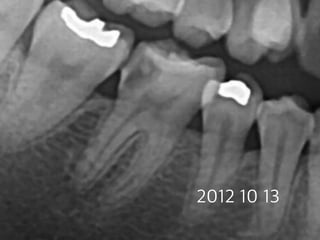

#30 Partial pulpotomy

follow-up case

(23 female)

2013 01 26

2012 10 13

23m later